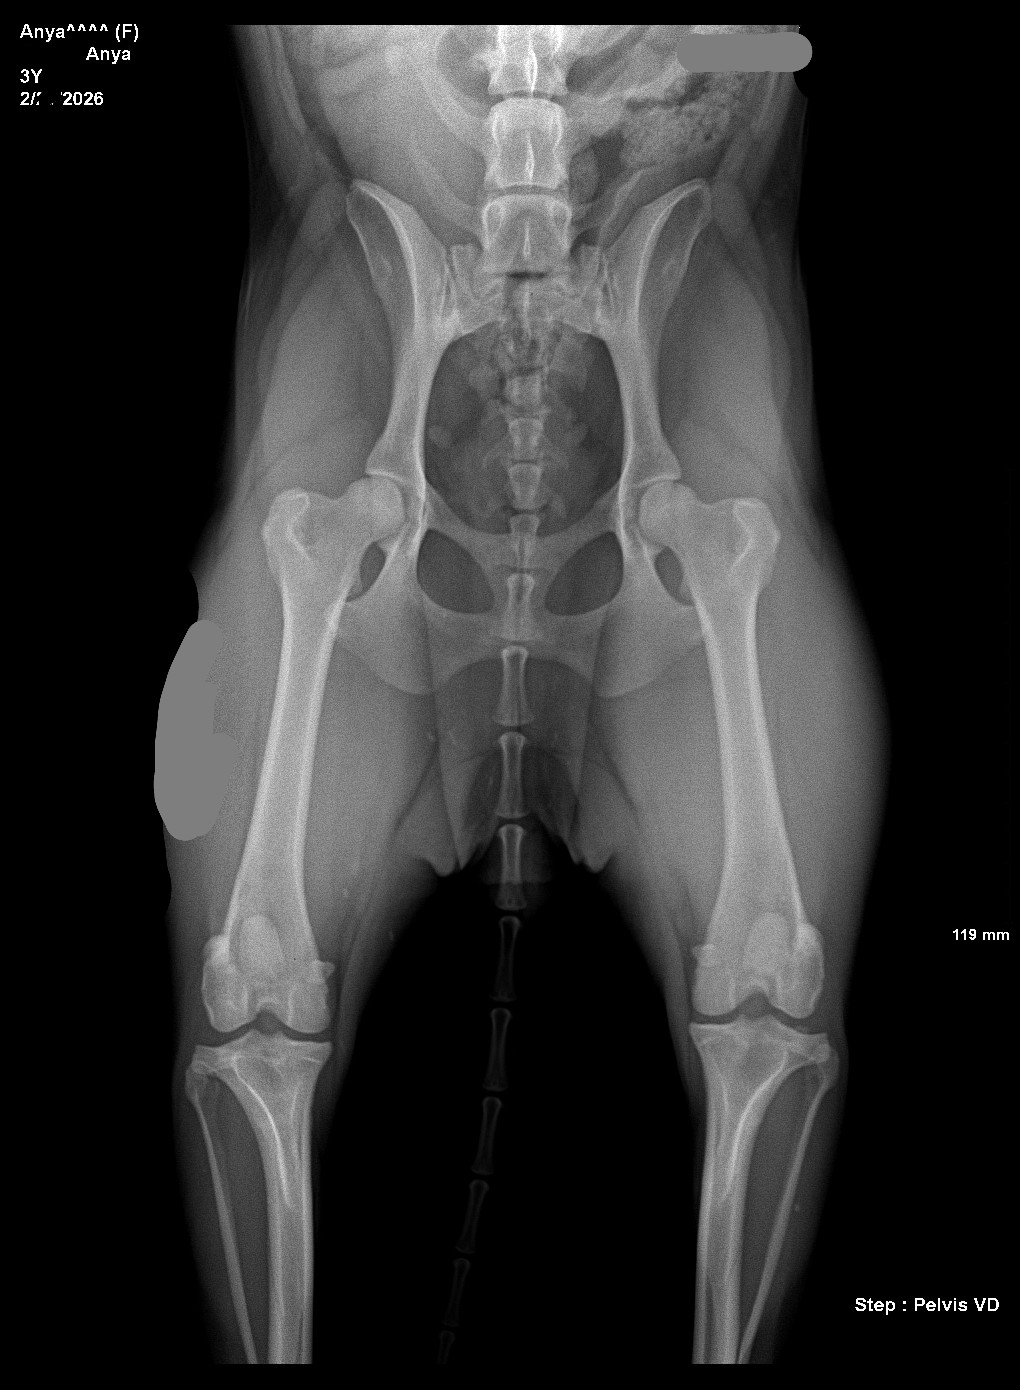

I'm one step closer to breeding Anya. The vet says she has good hips.

>>5107505What are you talking about? I want her to have little babies some day. All the professionals x-ray dog hips.